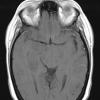

Astrocytoma, IDH-mutant, WHO Grade 2 (2)